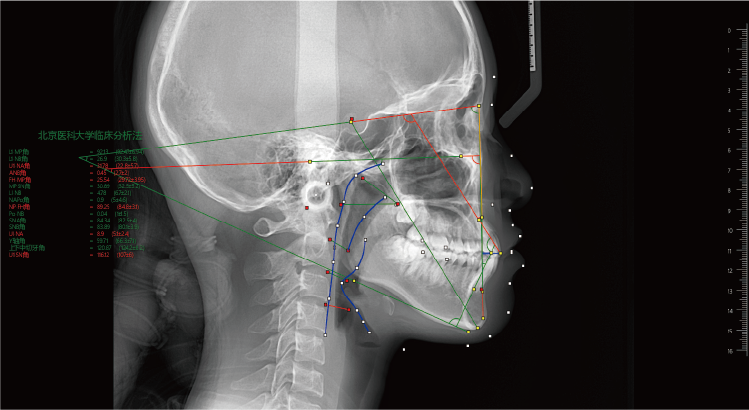

南京瑞德医疗自研的“智影”后处理软件、“慧影”正畸软件,底层架构完全自构、融合了多种AI技术,具备自动绘制双侧下颌神经管、TMJ双侧颞下颌关节分析、区域骨密度测量、可联动术前术后比对、AI牙弓线精准绘制、多平面模拟种植等功能,为医生快速有效决策提供助力,并支持影像图片、多种报告的一键扫码获取,让诊疗更加高效、便捷。

正畸软件自动描点生成报告